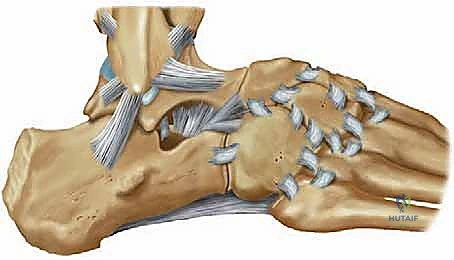

الأربطة الجانبية للكاحل (Lateral Ligament Complex)

تتكون الأربطة الجانبية، وهي الأكثر عرضة للتمزق أثناء التواء الكاحل للداخل (Inversion Sprain)، من ثلاثة أربطة رئيسية:

1. الرباط الكاحلي الشظوي الأمامي (ATFL): هو الرباط الأضعف والأكثر تعرضاً للتمزق. يمنع انزلاق عظمة الكاحل (Talus) للأمام.

2. الرباط العقبي الشظوي (CFL): رباط قوي يشبه الحبل، يربط بين عظمة الشظية وعظمة الكعب. يمنع الميلان المفرط للكاحل.

3. الرباط الكاحلي الشظوي الخلفي (PTFL): هو الأقوى ونادراً ما يتمزق إلا في حالات الخلع الكامل للمفصل.